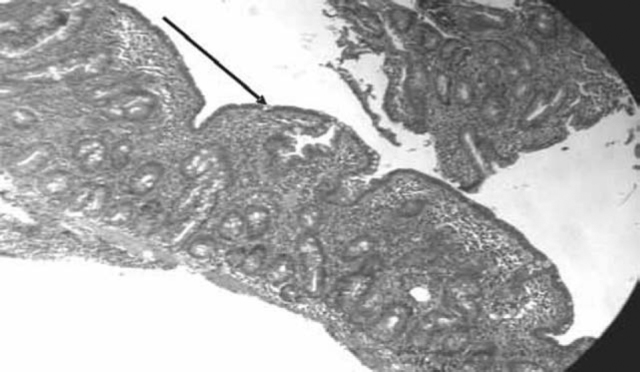

Fig. 1.

Duodenal biopsy under light microscope showing blunting of villi

Villous-crypt ratio was decreased in children with villous atrophy group in 81.25% while it was 1.96% in no villous atrophy group (p < 0.0000001). Intra epithelial lymphocytosis was seen in 81% children with villous atrophy group and 3.92% in no villous atrophy group (p <0.000001). Lymphomononuclear infiltration was observed in 87.5% children with villous atrophy group and 9.8% in no villous atrophy group (p <0.000001).

Intestinal biopsy is essential for the diagnosis of CD. Endoscopic findings associated with a high specificity for CD include scalloping of the small bowel folds, paucity in the folds, mosaic pattern, prominence of the sub mucosal blood vessels and a nodular pattern of the mucosa [7, 11]. Sensitivity of detection of CD with standard endoscope is 100% but the specificity is only 61% [12]. Histological examination further demonstrates a cellular infiltrate in lamina propria and blunting of villi. In the present study, 24% children had villous atrophy with decreased villous-crypt ratio in 81.25% and intra epithelial lymphocytic infiltration in 81% of them. These changes were statistically highly significant when compared with biopsies of children with no CD (p<0.000001). Troncone observed villous atrophy in 16% children suspected to be having CD clinically [19]. Intra epithelial lymphocytosis was observed in 38–100% by others [14, 15, 16, 17, 18]. Villous atrophy is not specific for CD. It can also be seen in other conditions like infections, infestations, tropical sprue etc. There is strong genetic association of CD (90–95%) with HLA-DQ2 (sensitivity 94%, specificity 73%) and DQ8 (sensitivity 12% and specificity 81%). While HLA typing is not recommended for routine diagnosis as it is cumbersome and costly, it can be used for ruling out CD where the diagnosis is equivocal. Screening is advised in high risk cases (Diabetes type-1, first degree relative of CD case, Down's syndrome), unexplained anaemia, unexplained failure to thrive, autoimmune thyroid diseases and unexplained neurological disorders. Gluten challenge is indicated when there is doubt about the diagnosis.